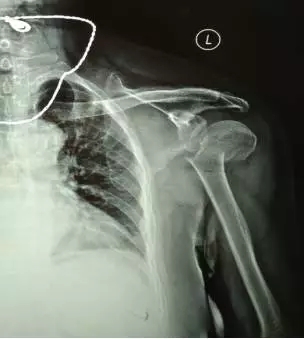

70多歲的鮑阿婆在家人陪同下來到上海大團醫(yī)院就診。大團醫(yī)院的醫(yī)生給鮑阿婆左肩部做了X線片檢查。片子拍出來竟然是左肱骨近端粉碎性骨折。外科頸,大結節(jié)都碎了,而且骨折端移位很嚴重。

正骨科的虞杰主任、邵鵬及葉華磊醫(yī)生看到鮑阿婆的片子也是一皺眉頭,這么厲害的骨折,還真是少見,而且移位這么嚴重,手法復位的難度也是相當大的。不過患者的信任給了他們很大的動力,即使困難也要盡力幫患者。

整復后復查X線片,骨折端位置良好。

整復前